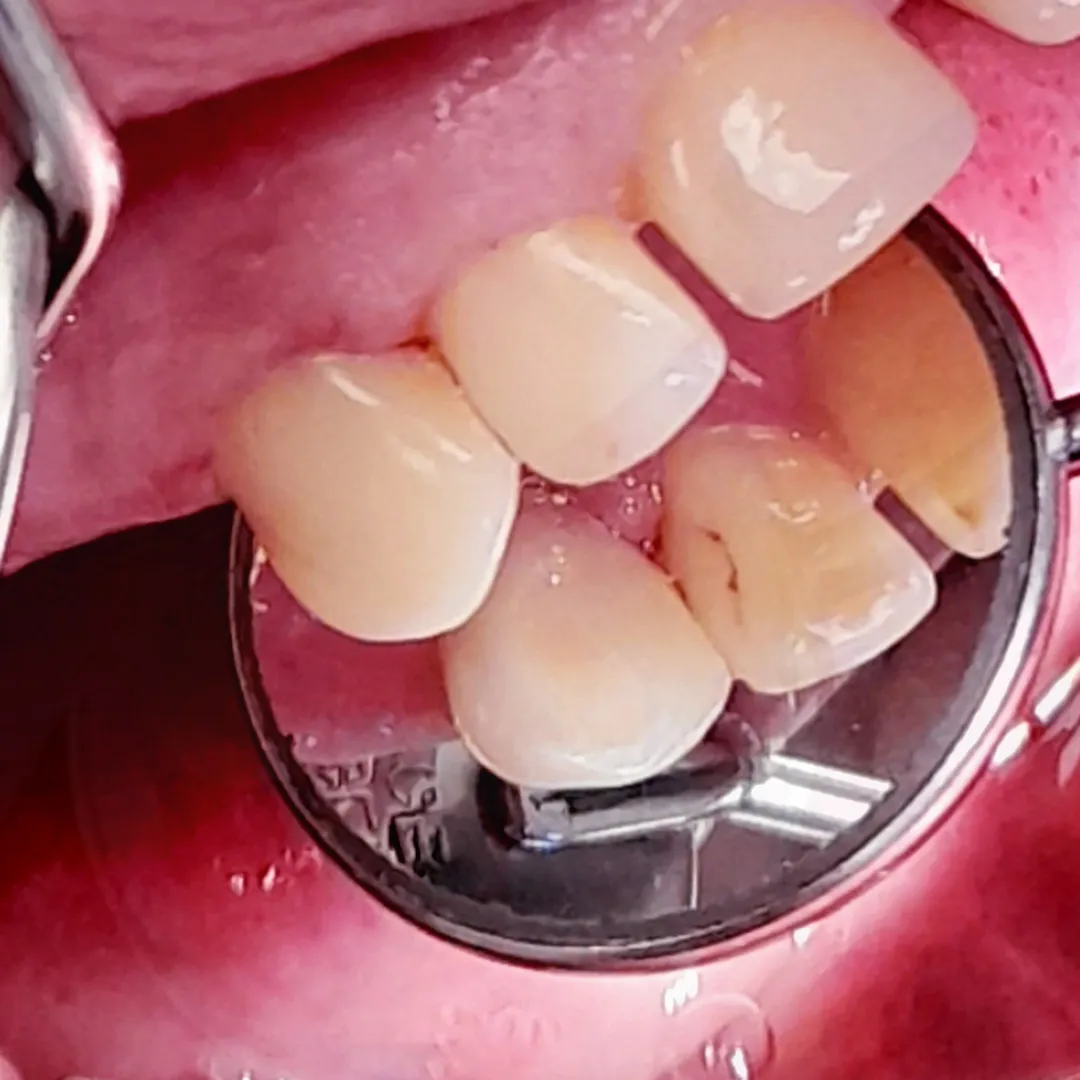

Замена несостоятельной пломбы перед установкой брекет-системыСмотреть работуСрок лечения:3 часаСумма лечения:16 500 руб.